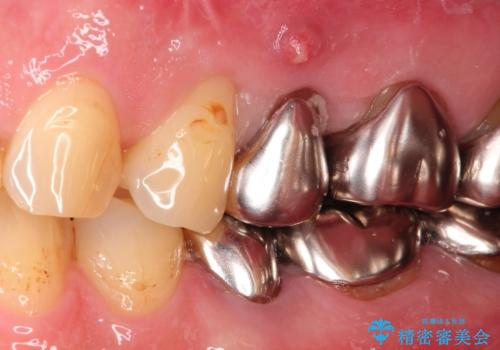

- 他院にて└5の治療を繰り返しても痛みがなくならないことを主訴に来院されました。

患歯はすでに2回の歯根切除術を受けており、長期的な予後不良となることから抜歯を選択されインプラントによる治療を行いました。

└6の不良補綴物も認め、根管治療及び補綴もやり替えてます。

インプラントによる治療は隣在歯を削らずに咬合回復できるという利点があります。

セラミッククラウンにより自然な見た目で修復できました。